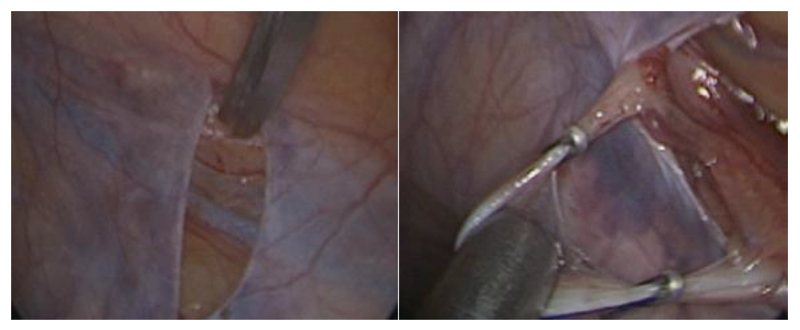

El paciente se ubica en decúbito dorsal con los brazos adosados al cuerpo y con un Trendelemburg moderado. Se punciona la cicatriz umbilical con un trócar de 2 mm de diámetro. Se efectúa el pneumoperitoneo y se inspecciona la pelvis con una óptica de 2 mm de 0 grados. En la fosa iliaca izquierda se instala otro trócar de 2 mm para una pinza ad hoc y en la fosa ilíaca derecha, un trócar de 5 mm para permitir el paso de un aplicador de clips de 5 mm.

Se ubica el orificio inguinal profundo y unos 2–3 cm hacia proximal de la reflexión del conducto deferente. Sobre los vasos espermáticos se efectúa una peritoneotomía de 1 cm. Se toma el cordón en bloque y con una suave contra tracción se aísla y preserva la arteria testicular utilizando un disector tipo Maryland. El resto del cordón se clipa y secciona en bloque.

Estaremos tratando todas las venas del cordón y seccionando la mayoría de los filetes nerviosos responsables en la inervación sensitiva del testículo. Solo quedarán indemne los nervios que transcurren junto con la arteria testicular que preferimos preservar. Revisión de la hemostasia con una baja presión del pneumoperitoneo y por último el retiro de los trócares bajo visión directa(46) (Figuras 32 y 33).